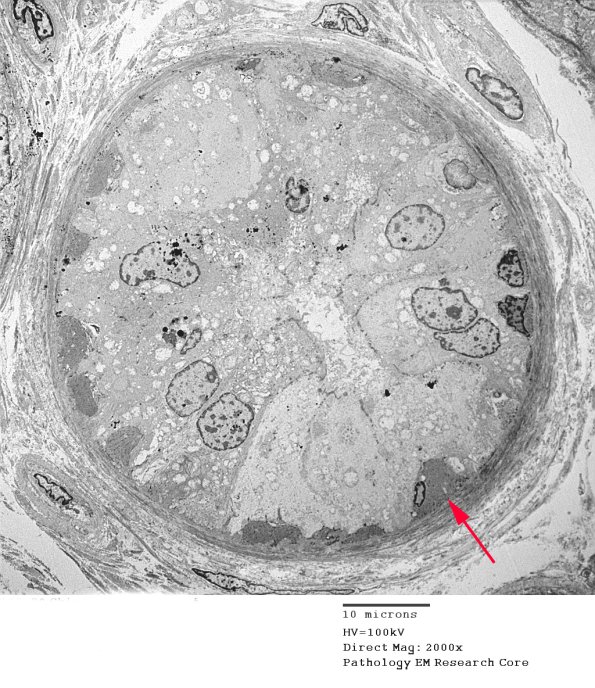

This is an eccrine gland with myoepithelial cells (arrow). (electron micrograph)